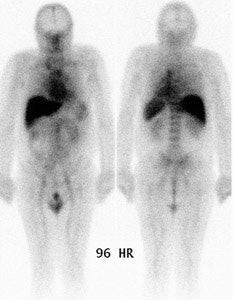

| Normal planar prostascint exam: Whole body planar imaging with normal biodistribution of the agent on 96 hour post injection imaging. |

- Planar images are first viewed to evaluate extra-abdominal and extra-pelvic structures. Mild blood pool and moderate bone marrow activity, and good visualization of blood filled structures (liver, spleen, penis) is expected. Mild to moderate large bowel activity is frequently seen, and may require bowel recleansing and further delayed imaging. Abnormal mesenteric and abdominal lymph nodes are often better seen on planar than SPECT images. Planar images are almost useless for prostate bed recurrence and pelvic metastasis.